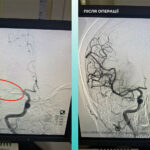

Медики выполнили тромбэктомию из мозговой и легочной артерий.

Одесситка попала в медучреждение с тяжелым острым мозговым инсультом, а во время обследования на компьютерном томографе врачи выявили закрытие средней мозговой артерии. Медики также зафиксировали, что пациентке тяжело дышать, поэтому дополнительно обследовали легкие и установили тромбоэмболию легочной артерии.

Мультидисциплинарная команда врачей приняла решение провести одновременную тромбэктомию из мозговой и легочной артерий. Операция прошла успешно, сейчас пациентка чувствует себя значительно лучше, она находится в сознании и уже двигает конечностями.